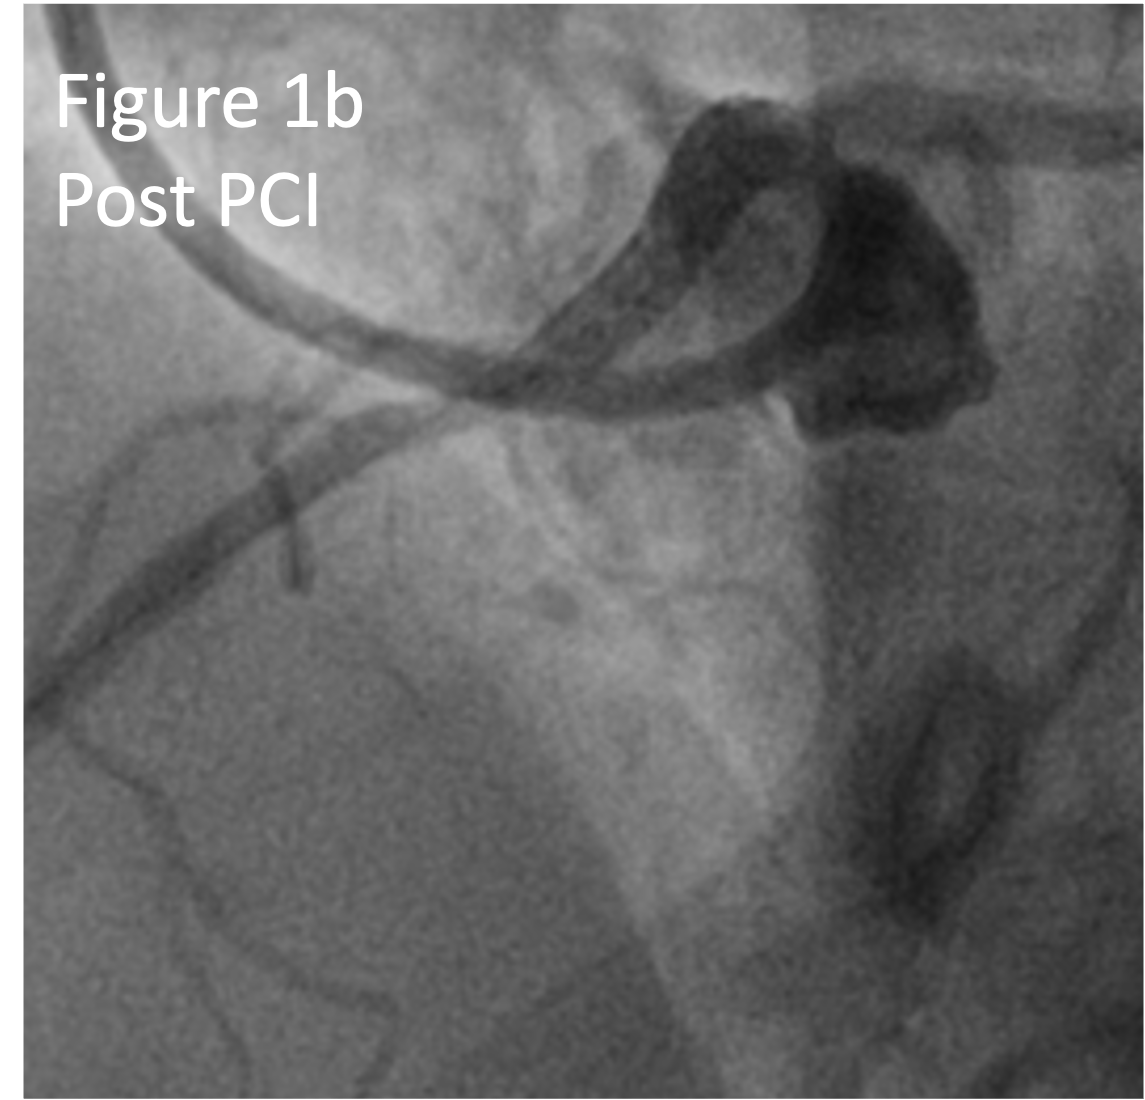

On representation a diagnostic coronary angiogram demonstrated a patent Left Main to Left Anterior Descending artery stent and severe stenosis in the ostial anomalous RCA (Figure 1a).

Intravascular ultrasound (IVUS) demonstrated severe ostial disease with a ¡°slit-like¡± appearance and a minimal luminal area (MLA) of 1.36mm2 (Figure 2a) with dynamic compression of the proximal RCA. The fibrotic RCA ostium was treated with a 3.5mm Wolverine Cutting Balloon. Real-Time IVUS ostial stenting was performed with a 3.5 x 16mm Megatron deployed. Post stent IVUS showed persistent dynamic compression at the ostium with a minimal stent area (MSA) of 6.53mm2 (Figure 2b). A 2nd 3.5 x 12mm Megatron was deployed over the 1st stent and post dilated with a 4.0 NC balloon to enhance its radial strength. Final IVUS showed minimal stent compression with an MSA of 8.1mm2 (Figure 2c). Final angiogram showed TIMI 3 flow (Figure 1b).